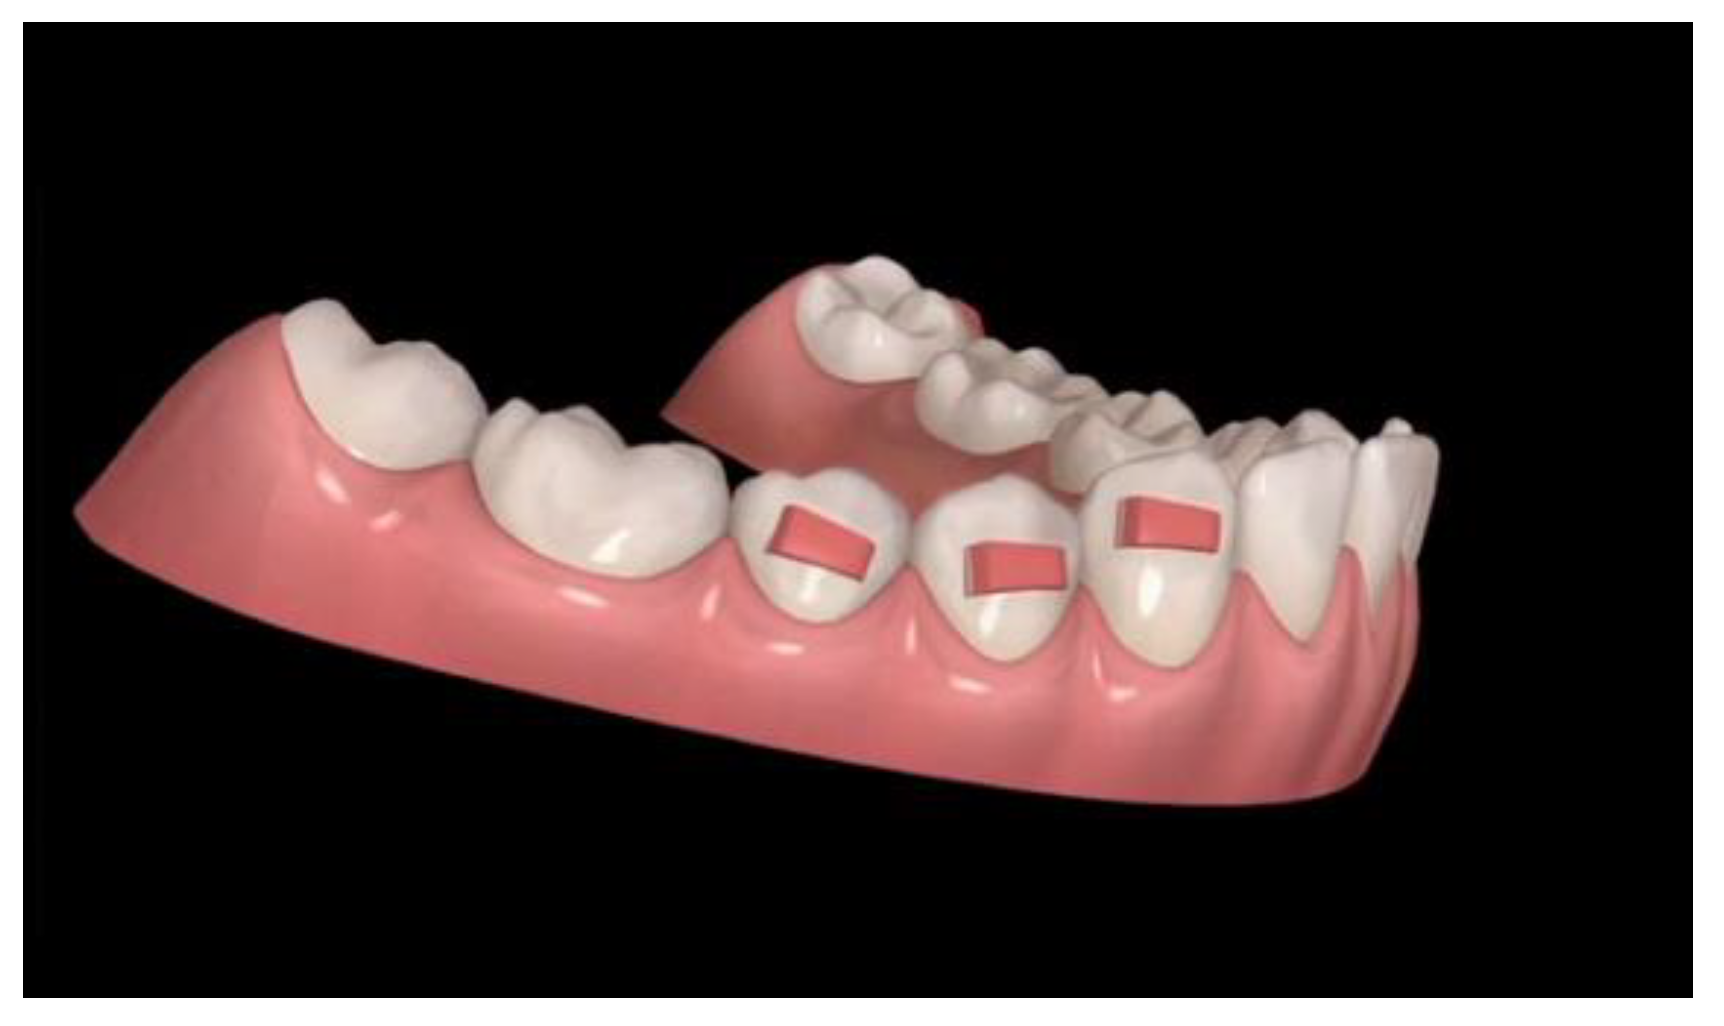

2.1. Attachments

Since aligners need retention to express vertical movements, such as extrusion or intrusion of posterior teeth, it is useful that the application of retention by conventional horizontal rectangular attachments are 4 mm large on premolars and, if possible, 5 mm on canines (Figure 4). If extrusion of the premolars is desired, the attachment design is modified from horizontal rectangular to gingival beveled (Figure 5). The attachments of this shape and dimension are necessary to improve the surface of force application to premolars and canines and to prevent dislodgement of aligners during an anterior intrusion.

Figure 4. Conventional horizontal rectangular attachments.

Figure 5. Different designs of lower premolars attachments.